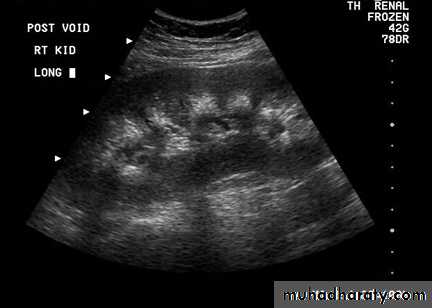

Nephrocalcinosis

Localization of the adenoma

Ultrasound

Neck MRI

99m Tc-sestamibi scintigraphy